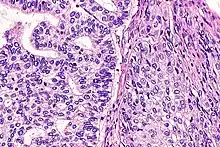

| Micrograph of a lung primary small cell carcinoma, a type of carcinoma. The clustered cancerous cells consist primarily of nucleus (purple); they have only a scant rim of cytoplasm. The surrounding pale staining, discoid cells are red blood cells. Cytopathology specimen. Field stain. | |

- Small cell carcinoma

- Cells are usually round and are less than approximately 3 times the diameter of a resting lymphocyte and with little evident cytoplasm. Occasionally, small cell malignancies may themselves have significant components of slightly polygonal and/or spindle-shaped cells.[8]